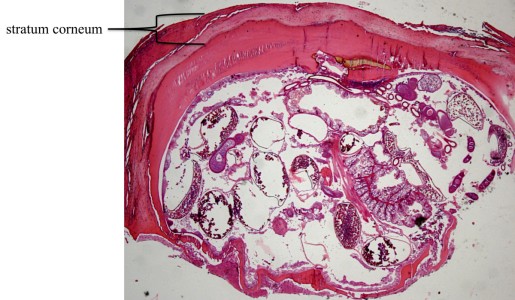

Het histologisch beeld wordt gekenmerkt door het vinden van Tunga penetrans in de epidermis of dermis. Het exoskelet, eieren in opeenvolgende stadia van ontwikkeling en delen van de tractus digestivus van de parasiet worden veelal gezien. Soms zijn er ook eieren te zien in het stratum corneum met onderliggende epidermale necrose. In circa 70% van de gevallen vertoont de epidermis afwijkingen, meest voorkomend zijn acanthose en parakeratose. Spongiose en hyperkeratose komen in minder dan 10-20% van de gevallen voor. In 30% wordt een onstekingsinfiltraat met neutrofielen of micro-abcessen gezien, meestal naast het exoskelet van de parasiet. De dermis vertoont een ontstekingsinfiltraat met voornamelijk lymfocyten, plasmacellen en eosinofielen.

Histologie tungiasis

ingescande coupe (zoom)

Bron hoge resolutie PA-foto: Kevin Kwee en Afdeling Pathologie MUMC. Klik op de afbeelding om in te zoomen.